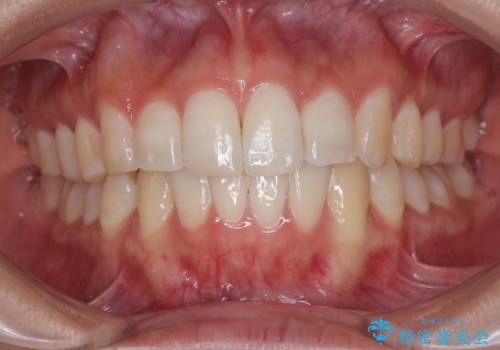

インビザライン・モデレートを用いて気になる後戻りを矯正治療

担当医 藤巻太一朗

前歯のガタつきを改善 抜歯矯正後の後戻り

担当医 草深敏毅